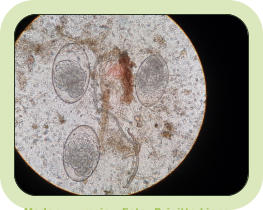

Um unsere Website zu vervollständigen, ist es erforderlich, Dich auch über weniger schöne Dinge zu informieren. Das sind Parasiten. Bei Parasiten kann es sich um Tiere, Pflanzen, Pilze oder Bakterien handeln. Eines haben alle Parasiten gemeinsam: Um zu leben, brauchen sie einen Wirt. Das können Menschen, Wild-, Haus- oder Nutztiere oder Pflanzen sein. Sprechen wir von Parasiten, sprechen wir von Schmarotzern. Man unterscheidet zwischen Außenparasiten (Ektoparasiten) und Innenparasiten (Endoparasiten). Wie der Name schon sagt, leben Außenparasiten äußerlich, z.B. auf der Haut des Wirtes. Das sind z.B. Zecken, Flöhe, Läuse und Blutegel. Sie ernähren sich vom Blut ihres Wirtes. Milben z.B. ernähren sich von Geweberesten, Pilzen, Pflanzen, Getreideprodukten oder Hautschuppen. Auf dem Speiseplan von Wanzen stehen Früchte, Blätter und Pflanzensäfte. Innenparasiten leben im Inneren des Wirtes. Zu den Innenparasiten gehören z.B. Maden-, Spul- und Bandwürmer sowie weitere Wurmarten. Sie befinden sich im Magen-Darm-Trakt oder befallen je nach Art andere Organe, z.B. die Lunge. Außenparasiten sind meinstens nur lästig und unangenehm. Anders ist es bei Innenparasiten. Sie können beispielsweise Ursache für Schmerzen im Magen-Darm-Trakt, Durchfall, Gewichtsverlust oder Blutarmut sein und können Krankheiten übertragen. Stellst Du Beschwerden dieser Art bei Dir oder Deinem Haustier fest, ist es wichtig, Deine Eltern zu informieren und Deinen Hausarzt bzw. den Tierarzt für Dein Heimtier aufzusuchen. Bei Wildtieren übernehmen diese Aufgabe die Betreiberinnen und Betreiber von Wildtierstationen und -pflegestellen. Sie haben die nötige Sachkunde und entscheiden gemeinsam mit dem behandelnden Tierarzt wie, womit und wie lange therapiert werden muss. Die bekanntesten Parasiten stellen wir in alphabetischer Reihenfolge vor. Außenparasiten (Ektoparasiten) Flöhe Stellvertretend für die vielen bekannten Floharten werden an dieser Stelle der Hasenfloh und der Hundefloh genannt. Der Hasenfloh… … auch Kaninchenfloh genannt, kommt in erster Linie bei Kaninchen und Hasen, insbesondere bei Wildkaninchen, vor. Man findet sie auch bei Marder, Iltis, Fuchs und Dachs. Mehr erfahren: https://www.deine-tierwelt.de/magazin/parasiten-beim-kaninchen-floehe/ Der Hundefloh Hundeflöhe sind zwischen zwei und vier Millimeter lang, bräunlich, flügellos, verfügen über einen seitlich abgeplatteten Chitinpanzer, sind in der Lage, sich blitzschnell fortzubewegen, springen erstaun- lich hoch und weit und ernähren sich vom Blut ihres Wirtes. Das sind in erster Linie Hunde. Weiterhin können u.a. Füchse, Katzen, Kaninchen und weitere kleine Nagerarten befallen werden. Mehr erfahren: https://www.stern.de/familie/tiere/floehe-beim-hund-bekaempfen--tipps-gegen-die-parasiten-30598580.html Läuse Die Hasenlaus Infos: file:///D:/Daten/Downloads/001-08-238-ocr-1.pdf Die Hirschlausfliege … auch Hirschlaus genannt, kommt in großer Zahl in Waldnähe vor. Befallen werden vor allem unterschiedliche Hirscharten, Dachs und Wildschwein. Auch Menschen können Opfer dieser blutsaugenden Insekten werden. Mehr erfahren: https://insektenschutz-gmbh.de/wissenswertes/insekten/die-fliegende-zecke-wie-gefaehrlich-ist-die-hirschlausfliege Milben Hast Du gewusst, dass Milben zu den Spinnentieren gehören? Schau mal vorbei. In der Rubrik erfährst Du mehr: Die Herbstgrasmilbe… … auch Erntemilbe genannt, befällt vorzugsweise kleine Säugetiere, beispielsweise Mäuse, Igel oder Kaninchen, Haustiere, beispielsweise Hunde und Katzen oder wenn auch weniger oft: Vögel. Auch Men- schen werden vor Befall mit diesen Plagegeistern nicht verschont. Mehr erfahren: https://frontline.de/milben/herbstgrasmilben Extremer Milbenbefall bei einem Igel Foto: Brigitte Liepe, Igelhilfe Eschweiler I Die Krätzmilbe Krätze ist mit bloßem Auge nur schwer erkennbar, denn es handelt sich um feine, dunkle, unregelmäßige Linien in der Haut. Wird nicht behandelt, entstehen winzige Bläschen, gerötete Knötchen und Pusteln. Krätze ist vergleichbar mit Milbengängen in der Haut. Mehr erfahren: https://www.aok.de/pk/magazin/koerper-psyche/haut-und-allergie/kraetze-ansteckung-und-vorbeugung/ Rote Vogelmilbe Wie der Name schon ahnen lässt, befällt dieser blutsaugende Außen- parasit meistens Vögel. Befallen werden Singvögel, Hühner und Ziervögel. Die Rote Vogelmilbe befällt auch Säugetiere und Menschen. Mehr erfahren: https://de.wikipedia.org/wiki/Rote_Vogelmilbe Zecken Hast Du gewusst, dass Zecken zu den Spinnentieren gehören? Schau mal vorbei. Auf dem Foto rechts siehst Du eine durstige Zecke in Originalgröße. Sie ist nicht größer als ein Stecknadelkopf. Ist sie in die Haut einge- drungen, saugt sie sie voll und fällt wieder ab. Von der Menge des Blutes kann sie sich sehr lange ernähren. Innenparasiten (Endoparasiten) Der Madenwurm Madenwürmer sind klein (ca. 10 mm), dünn, weiß und entwickeln sich innerhalb weniger Stunden. Sie leben im Magen-Darm-Trakt ihres Wirtes. Die weiblichen Madenwürmer kriechen aus dem Po ihres Wirtes und legen ihre Eier im Bereich der Analfalten, also in der Umgebung des Darmausgangs ab. Der entstehende Juckreiz führt z.B. bei Hunden zum sog. „Schlittenfahren“. Dein Hund rutscht auf dem Po, um sich auf diese Weise Erleichterung zu verschaffen. Madenwürmer kommen auch bei Menschen, vorzugsweise bei Kindern, Madenwurmeier, Foto: Brigitte Liepe vor. Ansteckung erfolgt von Mensch zu Mensch. Der Spulwurm Hast Du gewusst, dass weibliche Spulwürmer bis zu 40 cm lang werden und für die häufigsten Wurminfektionen weltweit, vor allem bei Kindern, verantwortlich sind? Über verunreinigte Lebensmittel gelangen Eier von Spulwürmern in den Körper des Wirtes und ent- wickeln sich dort zu Würmern. Spulwürmer legen Eier im mensch- lichen Darm ab. Die Eier werden ausgeschieden und reifen außer- halb des Körpers. Der Wirt infiziert sich, wenn reife Eier über verunreinigte Lebensmittel aufgenommen werden. Die Ansteckung von Mensch zu Mensch ist daher ausgeschlossen. Der Bandwurm Selten, aber aus gesundheitlichen Gründen nicht zu unterschätzen, sind Infektionen mit dem Fuchs- oder Hundebandwurm. Die Ansteckung kann durch Verzehr von ungewaschenen Beeren, Fallobst, Früchten oder rohem Fleisch erfolgen. Der Bandwurm verursacht unter Umständen erst Jahre nach der Infektion Zysten an verschiedenen Organen im Körper. Eine lebenslange Medikamen- teneinnahme könnte die Folge sein… Haarwürmer Hast Du gewusst, dass Haarwürmer so heißen, weil sie so extrem fein sind? Die Eier von Haar- würmern werden mit dem Kot ausgeschieden. Im Freien bildet sich nach etwa fünf bis sieben Wochen das infektiöse Larvenstadium. Oft sind Regenwürmer sogenannte Transportwirte. Mit der Nahrung nimmt der Endwirt, oft sind es Igel, die infektiösen Eier auf. Man unterscheidet Darmhaarwürmer und Lungenhaarwürmer. Der Darmhaarwurm 20 bis 26 Tage nach Aufnahme der infektiösen Eier haben sich erwachsene Würmer im Darm entwickelt und Geschlechtsprodukte, die Eier, sind im Kot nachweisbar. Erwachsener Darmhaarwurm Foto: Brigitte Liepe Der Lungenhaarwurm Etwa drei Wochen nach Aufnahme sind infektiöse Eier des Lungen- haarwurms im Kot nachweisbar. Lungenwurmlarve Foto: Brigitte Liepe Saugwürmer… … sind Plattwürmer, die je nach Art in unterschiedlichen Organen, z.B. im Darm, der Leber oder der Lunge vorkommen. Am häufigsten ist sicher der Darmsaugwurm verbreitet. Der Darmsaugwurm Um sich zu erwachsenen Darmsaugwürmern entwickeln zu können, benötigen sie Zwischenwirte. Das sind Schnecken. Unreife Würmer werden vom Zwischenwirt freigesetzt und vom Endwirt, häufig sind es Igel, aufgenommen. Im Endwirt reifen Darmsaugwürmer zu erwachsenen Tieren heran. Wird nicht dagegen behandelt, richten sie im Körper ihres Wirtes erheblichen Schaden an. Darmsaugwürmer können sehr alt werden. Mehr erfahren: https://parasitenfotos-fuer-paeppler.de/parasiten-portraits/der-darmsaugwurm-brachylaemus-erinacei-fluke/ Der Hakenwurm In der Tierwelt sind vor allem Hunde und Katzen von Hakenwurm- infektionen betroffen. Die Wurmart hat keinen Zwischenwirt. Die weiblichen Tiere sind bis zu 10 mm lang, die Männlichen etwas kürzer. Symptome sind Blutarmut und Dein Tier wirkt grundlos müde. Hakenwürmer machen vor Menschen nicht halt. Mehr erfahren: https://de.wikipedia.org/wiki/Hakenw%C3%BCrmer Der Kratzwurm… Kratzwürmer auch Kratzer genannt befallen als Zwischenwirte verschiedene im Wasser lebende Insekten und Krebstiere, als Endwirte Fische, Amphibien, Vögel und Säugetiere. Weltweit sind inzwischen etwa 1.100 Arten bekannt. Die Körperlängen reichen von wenigen mm bis etwa 70 cm. Mehr erfahren: https://de.wikipedia.org/wiki/Kratzw%C3%BCrmer